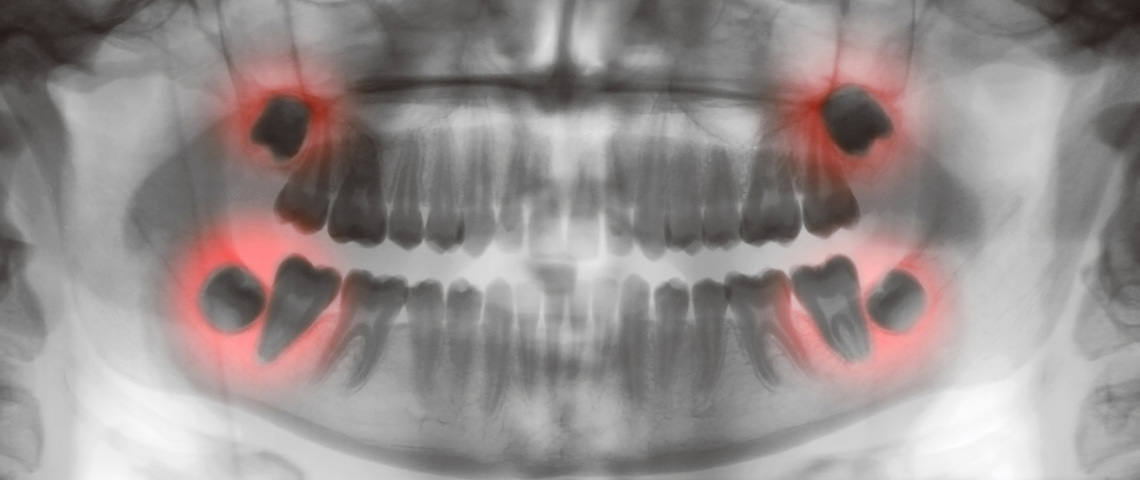

Os dentes do siso são os terceiros molares de cada lado dos maxilares. São também os últimos dentes a nascer, geralmente entre os 16 e 20 anos de idade.

Por serem os últimos dentes a nascer, habitualmente não há espaço suficiente na boca para acomodá-los. Isto pode fazer com que os dentes do siso fiquem inclusos - dentes presos em baixo do tecido gengival por outros dentes ou osso. Se os dentes estão inclusos, pode ocorrer inchaço ou flacidez.

Os dentes do siso que erupcionam apenas parcialmente ou nascem mal posicionados, também podem causar problemas. Como os dentes removidos antes dos 20 anos de idade têm raízes em menor estágio de desenvolvimento e causam menos complicações, recomenda-se que as pessoas entre 16 e 19 anos tenham os seus dentes do siso examinados para verificar se precisam de ser removidos.